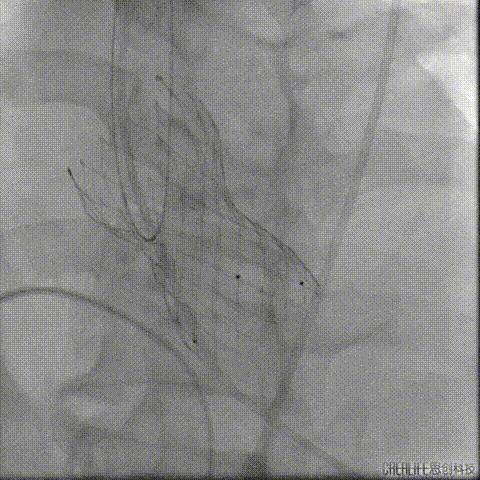

经瓣架网眼挂上指引管

反复确认指引管经瓣架网眼

指引管经瓣架网眼

经网眼置入导丝

置入4.0mm*23mm微创冠脉支架

定位并释放支架

退出球囊扩张突入瓣架部位

复查冠脉造影

多体位复查冠脉造影